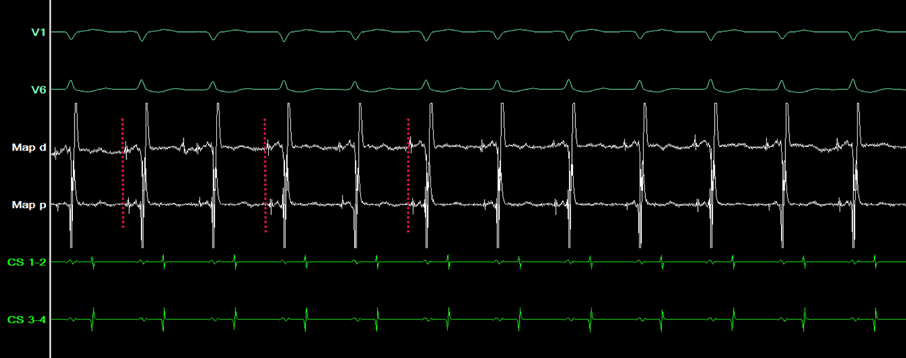

Unter atrialem burst-pacing zeigt sich ein leicht verlängertes HV-Intervall im Vergleich zum HV-Intervall während der Tachykardie. Die His Aktivierung während der Tachykardie verläuft retrograd, d.h. von distal nach proximal (Abbildung 4).

EP-Fall_7_24_4

Abbildung 4: Intrakardiale Signale während der elektrophysiologischen Untersuchung. Der Mapping-Katheter wurde im Bereich des His platziert. Während der Tachykardie zeigt sich eine retrograde His-Aktivierung (rote Markierung). 50 mm/s. Map d = Intrakardiale Signale des Mapping-Katheters, distal Map p = Intrakardiale Signale des Mapping-Katheters, proximal CS: Intrakardiale Signale des Koronarvenensinus-Katheters.